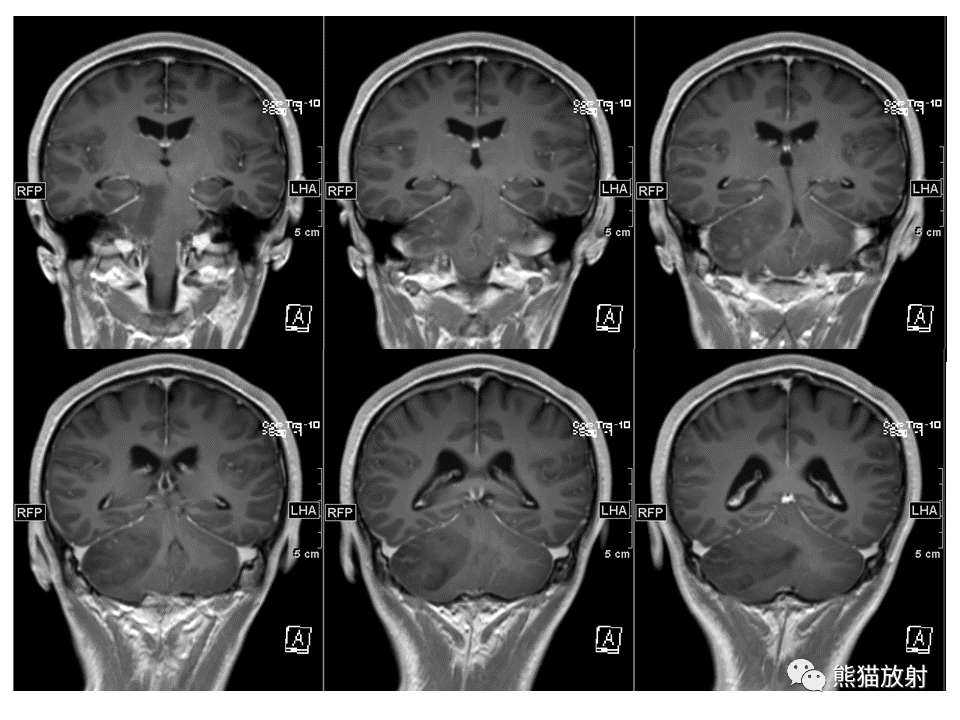

【PPT】小脑发育不良性神经节细胞瘤 VS 成人型髓母细胞瘤-3